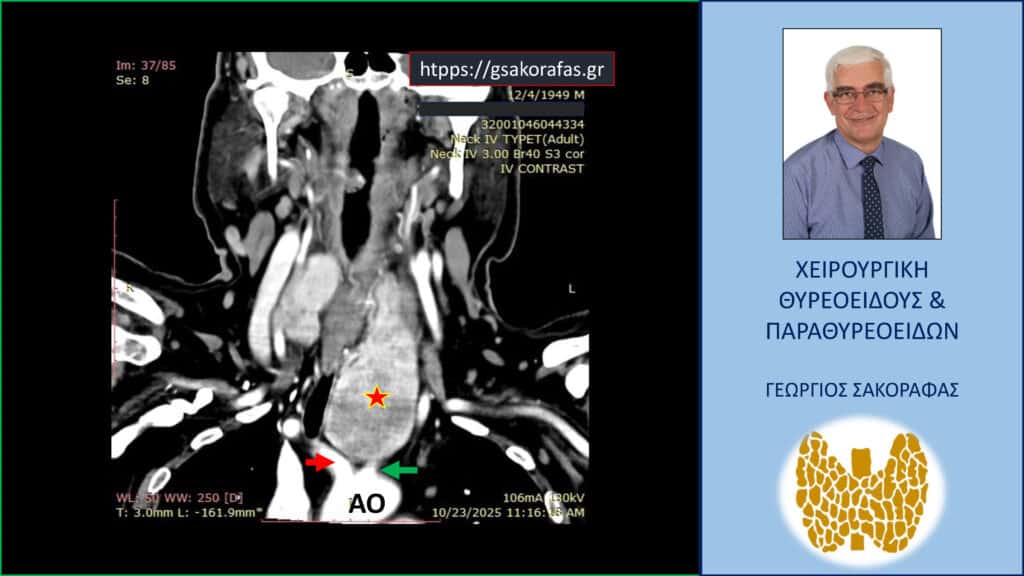

- Γιατί είμαστε σε θέση να εκτελέσουμε με ασφάλεια και αποτελεσματικότητα κάθε είδους χειρουργική επέμβαση θυρεοειδούς – παραθυρεοειδών, ακόμη και σε επιπλεγμένα (δύσκολα) περιστατικά, όπως εκτεταμένοι λεμφαδενικοί καθαρισμοί σε καρκίνο θυρεοειδούς, επεμβάσεις σε λίαν ευμεγέθεις καταδυόμενες στο μεσοθωράκιο βρογχοκήλες, υποτροπές παθήσεων θυρεοειδούς (συμπεριλαμβανομένου του καρκίνου θυρεοειδούς), υποτροπές υπερπαραθυρεοειδισμού, αδενώματα παραθυρεοειδών σε έκτοπη θέση ή λόγω υπεράριθμων παραθυρεοειδών, διάχυτη υπερπλασία παραθυρεοειδών, κλπ.